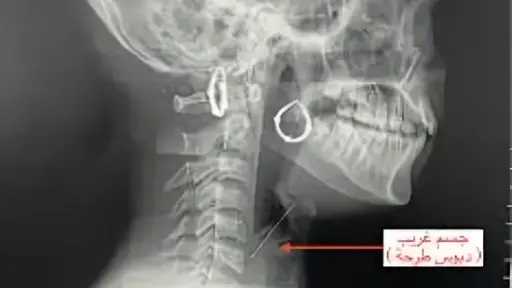

الدورة الثانية من المضاعفات جعلتنى أرى بُعدًا ثالثًا ورابعًا لهذه اللوحة. وأنا بين الحياة والموت، بدا لى أن أينشتاين كان على حق فى نسبية الزمن، الذى ارتبط فى نظريته بالحركة، شارحًا أن الزمن يتقلص حسب سرعة الحركة، التى إن وصلت إلى سرعة الضوء يتوقف الزمن. ولكنى وفى حالتى وأنا بين الوعى واللا وعى لم أحتَج إلى الحركة لأكتشف نسبية الزمن، فقد كانت الأحداث حولى تمر، والإجراءات الطبية تُتخذ، وأنتقل من الأشعة المقطعية إلى الموجات الصوتية إلى محاولات إيجاد طريق إلى جهازى الدورى وتركيب أنابيب وتقليب فى سرير المرض وذهنى يتصور أنه قد مر يوم، إلى أن أكتشف أنها كانت دقائق، وأن الساعة مازالت فى بداية اليوم.. كيف لا يمر الزمن، وكيف لا تمر الأيام وأنا فى حالتى هذه؟!!!.